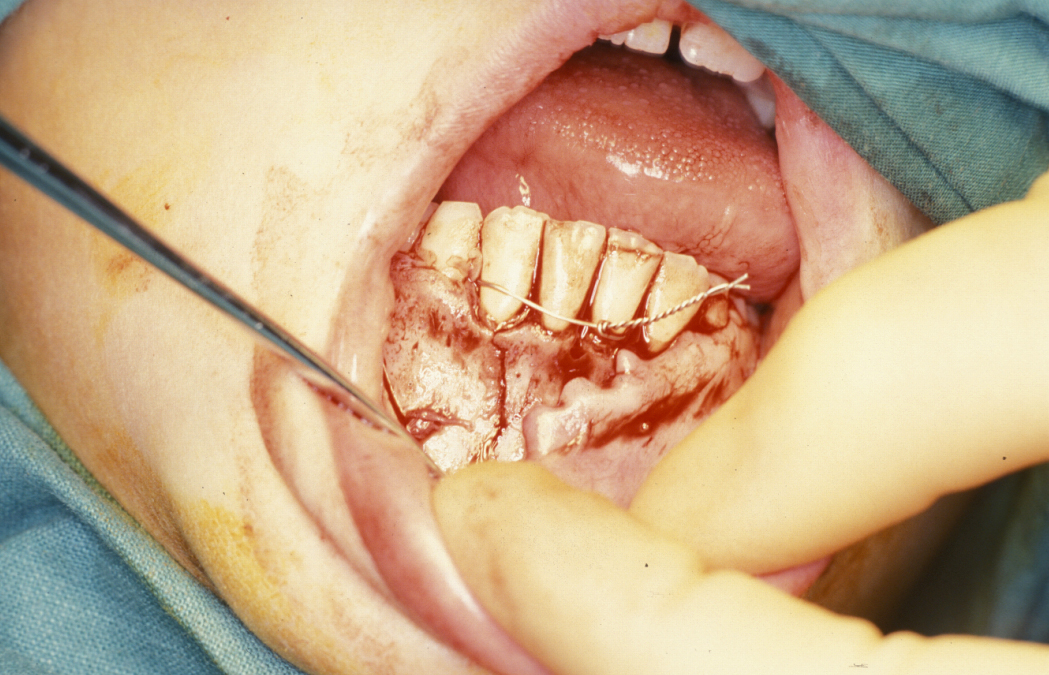

Displaced, mobile fractures are very painful. The placement of temporary stabilising wires around the teeth adjacent to the mandibular fracture will immobilize the fracture and make the patient more comfortable while awaiting definitive surgery under general anaesthesia. This can help to reduce the need for analgesics in the preoperative period.

Definitive surgery usually involves open reduction and internal fixation (ORIF) under general anaesthesia, ideally using nasoendotracheal intubation. This allows the patient’s mouth to be closed and the teeth to be manipulated into their normal occlusion. This manipulation helps reduce the mandible into the prefracture bone position. Temporary intermaxillary fixation (IMF) is applied using a variety of techniques (trainee’s hand, eyelets, transalveolar screws (see Figure 1 and Figure 2), ‘rapid IMF’, arch bars). This helps to hold the fracture in its reduced position. Placing a bridle wire or tension band around the teeth can help reduce and temporarily fix the fracture.